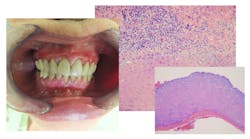

Recognizing the subtle differences between look-alike conditions is vital for accurate referral and diagnosis. Two red lesions—erosive lichen planus (OLP) and erythematous candidiasis—can appear deceptively similar. But they have fundamentally different origins, implications, and management approaches (figure 1).1

Erosive lichen planus typically presents as well-demarcated erythematous or ulcerative lesions, often accompanied by Wickham’s striae—a network of fine, white, lace-like lines on its reticular type. These lesions most often affect the bilateral buccal mucosa but can also involve the gingiva (as desquamative gingivitis), tongue, and labial mucosa. Patients frequently report pain, especially during eating or when exposed to spicy or acidic foods.

In contrast, erythematous candidiasis appears as diffuse, red, atrophic areas and gives a burning sensation. The affected area may appear smooth and thinned, especially on the cases affecting the dorsum of the tongue, palate, and buccal mucosa. Lesions are typically asymmetrical and may correlate with local risk factors such as denture coverage, antibiotic use, or immunosuppression. Unlike OLP, candidiasis rarely presents with white striae or ulceration.2

A biopsy is often recommended for lichen planus, especially in cases of erosive or ulcerative lesions, to rule out dysplasia or squamous cell carcinoma. Unlike candidiasis, there are no fungal elements present under the microscope. Candidiasis is often a clinical diagnosis and can be confirmed with a simple cytology smear that reveals fungal hyphae.